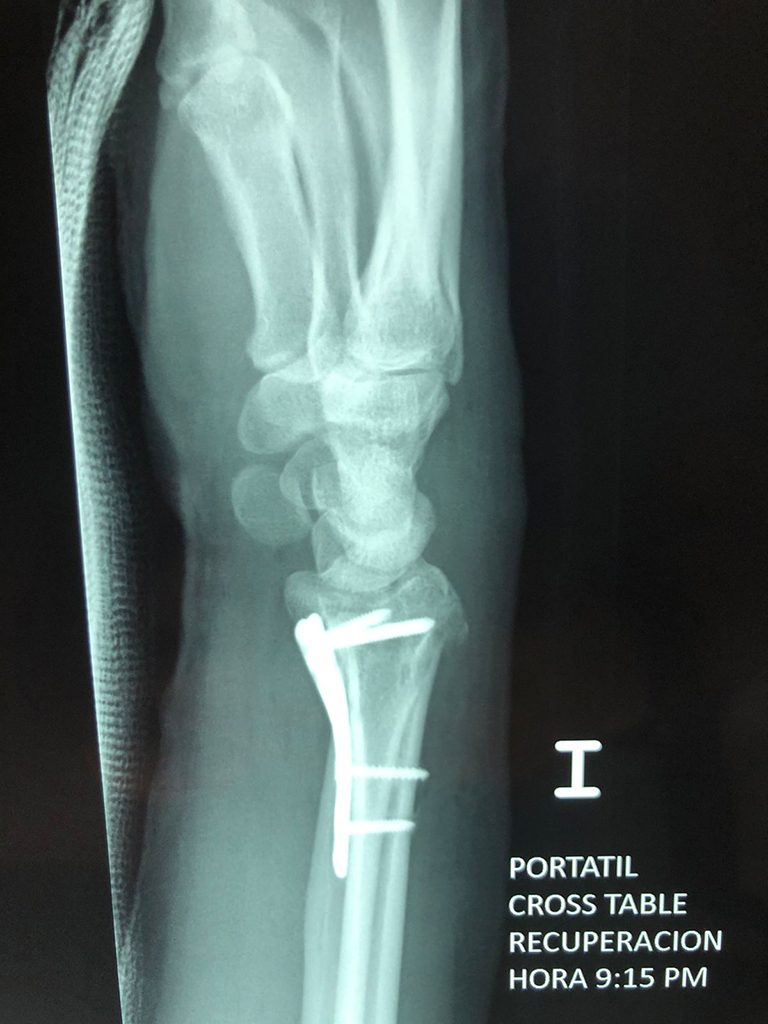

Cirugía de Tibia y Peroné

Los procedimientos más comunes en cirugía de la mano son aquellos destinados a reparar traumatismos, incluyendo lesiones de tendones, nervios, vasos sanguíneos, y articulaciones; huesos fracturados; y quemaduras, cortes, y otros daños de la piel.